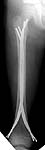

Date: Wed, 20 Jun 2001 23:19:13 -0700

From: Carlo Bellabarba

alex,

here's a recent Ender example with three-month followup. sorry about the

quality of the injury image--there were better outside films that have since

disappeared. I still think this technique is useful, even in rotationally

unstable patterns such as this one. i take the nails out at 6 mos, and leave

them a little proud on purpose (this 10 year-old is a bit of chunkster so

they don't bother him) and suture them down so that they don't back out

more.

it aren't fancy, but it's quick and seems to work.

carlo bellabarba